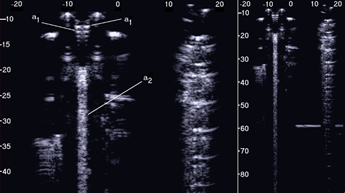

The first test shows what happens when a single row of air cylinders is introduced in the agar gel. The image on the left of Figure 3 shows that in this case, there are no artifacts except the short ones which are generated by multiple reflections between two contiguous air cylinders. In particular, no artifact is generated by a single air cylinder. The situation changes, however, as a row of air cylinders is added, and increasingly longer artifacts are observed as the number of rows of cylinders increases. The two images in the centre and on the right of Figure 3 show the artifacts which were obtained with two and with four rows of air cylinders, respectively. A repetitive pattern is still perceivable, but it is not clearly quantifiable. The thick white lines at the bottom of the three images are given by the reverberations within the bottom wall of the box.

Figure 3. The image on the left shows how a single row of air cylinders does not generate vertical artifacts. The two images in the centre and on the right show the artifacts obtained with two and with four rows of air cylinders. A different zoom degree has been used for the image on the right.

Figure 4 shows some configurations which were tested and the obtained artifacts. Here, it can be observed how traps with the same input channel provide different artifacts as the shape of the trap changes. Artifact A was obtained with three staggered air cylinders. The artifact is short, and it is the only one that shows the characteristic modulation of cardiogenic artifacts. The modulation is most likely related to the simplicity of the trap which favours the constructive sum of the echoes, while its length is not easy to interpret. Artifacts B and D are generated by configurations of air cylinders which form two channels with rough lateral surfaces and the different lengths suggest their probable origin. The two artifacts are probably generated by multiple reflections between the walls of the channels during the propagation of the acoustic wave from the top to the bottom of the two channels. Artifact C is generated by a configuration of cylinders similar to that illustrated on the left of Figure 1 with cylinders of a larger diameter. Here, it can be observed how a larger trap with a more complex internal geometry than trap A provides a longer and more confused artifact. Artifact E was generated by a configuration of air cylinders obtained by eliminating the two cylinders that form the input channel of the trap that generated artifact C. This example shows how very different artifacts can be obtained when varying the shape and the size of the access channel. The F artifact is particular since in this case the US energy can be transmitted to the trap through the two small (0.5 mm large) lateral channels and through the larger (2 mm large) central channel. In this case, the artefactual information can be seen as three close but different artifacts or as a single complex artifact.

Figure 4. Six different arrangements of air cylinders immersed in agar gel and the obtained artifacts are shown. The black dots indicate the position of the air cylinders.